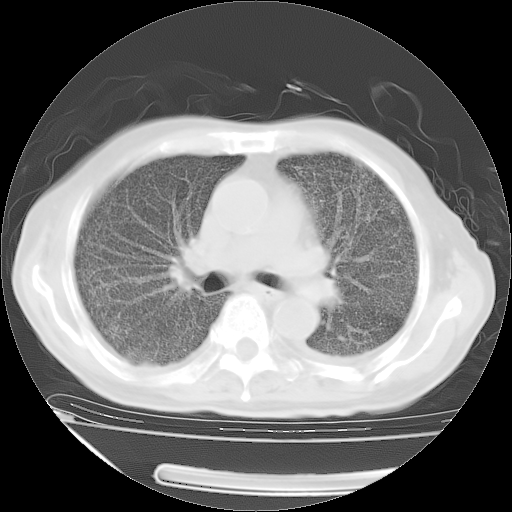

经过24天治疗,岳父的病情基本稳定。生活基本可以自理,可以下床活动。呼吸困难早已消失。体温基本正常。

只是甲强龙用80mg时血小板升到正常,改为60mg后又降到63×10*9/L。

主要治疗甲强龙80mg×14天,60mg×10天;同时抗结核(异烟肼+利福平+乙胺丁醇)。环磷酰胺0.1 tid 10天。

特别感谢胡教授、高管、桃子版主给出关键的治疗建议。桃版把所有肺部影像和全部临床资料请所在医院呼吸科、感染病科、结核科、临床免疫科专家会诊。临床免疫科专家制定了完整的治疗方案。